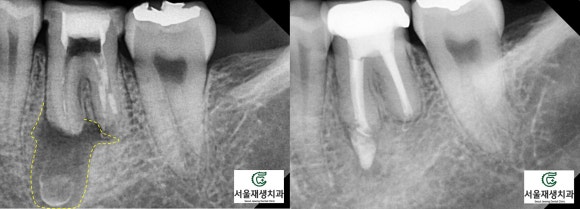

3개월이 엑스레이 상으로 유의미하게 병소(=염증물혹)이 사라지고, 새롭게 뼈가 차오르는 것을 확인하기 위한 최소 시간 단위이기 때문입니다.

그러나 병소의 크기가 작다던지, 나이가 젊어 엄청나게 빠른 속도로 치유가 진행되거나 하면 한 두 달 안에 끝나는 경우도 있습니다.

(빠른 치유 속도로 4주 만에 마무리되었던

케이스였습니다^^)